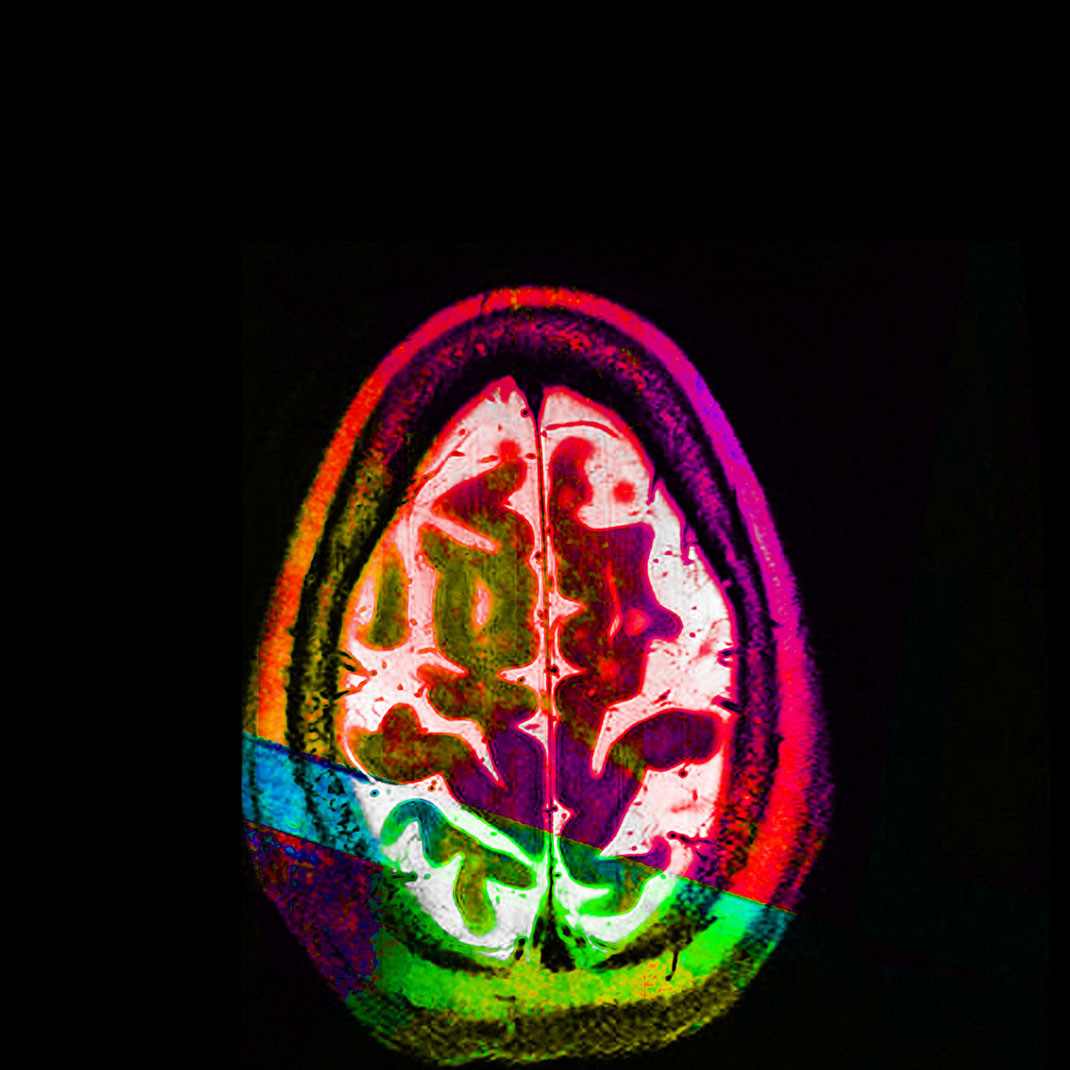

Elle trouve alors sa source d’inspiration dans sa maladie à travers ses IRMs. « Mes nombreux traitements m’ont donné envie de réinterpréter l’imagerie médicale. Les patients, souvent anxieux, ne voient que laideur et effroi dans les pixels noirs et gris des IRMs. J’ai alors ressenti le besoin vital de les utiliser pour montrer les merveilles et la beauté de nos cerveaux, y compris ceux souffrant d’une maladie. Je veux guérir les patients de la peur de regarder leurs IRMs », s’émeut Elizabeth.

En réutilisant ses scanners, Elizabeth Jameson cherche à insuffler des émotions et des sentiments dans la froideur technologique. Pour cela, elle utilise de nombreux supports : la peinture sur soie ou encore des impressions à partir de gravures sur cuivre ou sur plaque solaire. Ensuite, elle renforce la couleur de ses images grâce à de la peinture, des crayons ou du pastel sec. Le résultat offre une collection brillante, colorée, pleine d’émotion et de symbole.

Maintenant tétraplégique, Elizabeth crée avec l’aide d’un assistant. Selon elle, ses impressions ne sont pas qu’un moyen de faire la chronique des changements de son cerveau, qu’elle qualifie d’« organe le plus sacré ». Son travail est également un moyen de devenir plus familière avec ces changements, pour les rendre moins terrifiants. « Mon art est composé à 90 % de mon cerveau, tout simplement parce que je suis mon cerveau », conclut-elle.